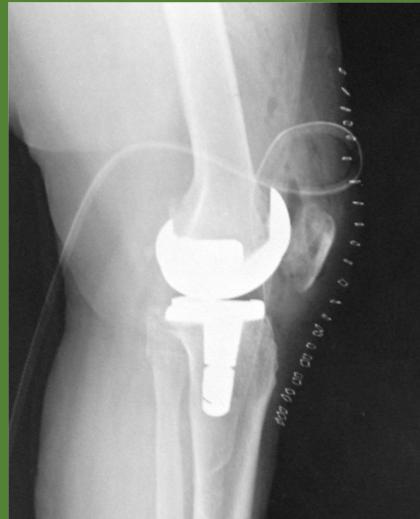

2. Osteoarthritis (OA)

- A weaker indication for steroid injection

- ✓ Prosthetic joint